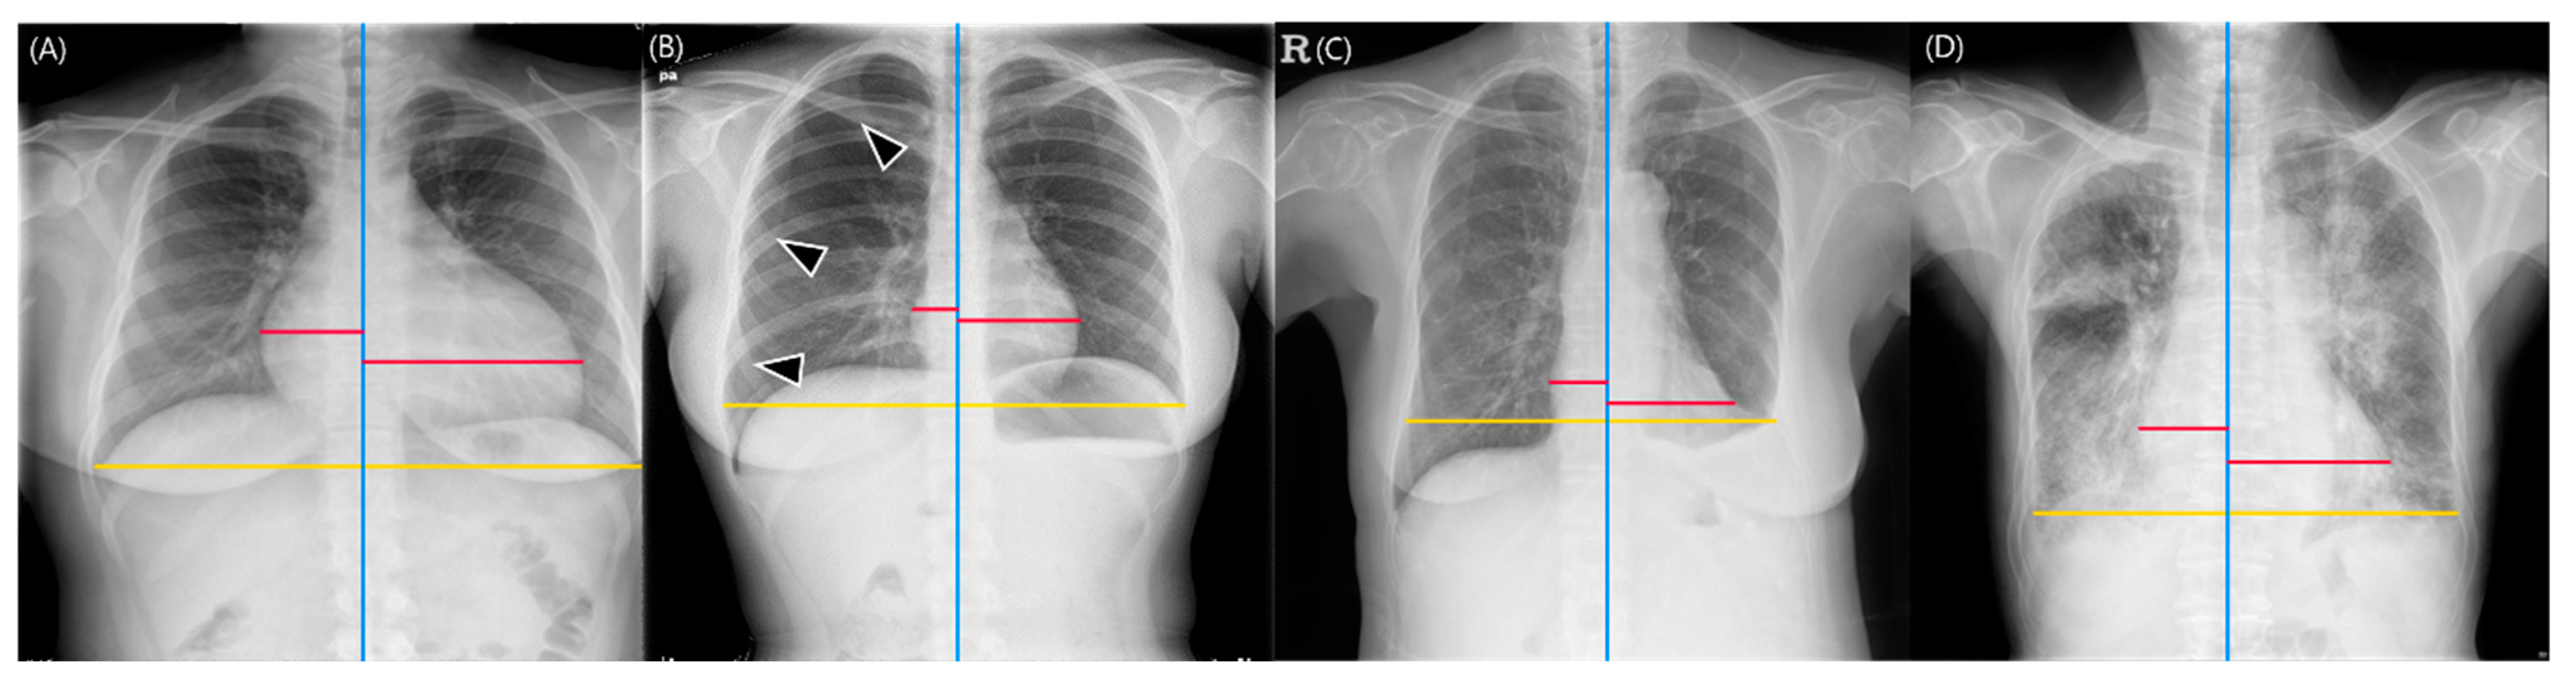

With the reference standard for cardiomegaly constructed from the Dawid–Skene consensus method, the DL-based model showed a sensitivity of 96.3% (95% CI: 89.7%, 99.2%), specificity of 83.3% (95% CI: 73.2%, 90.8%), PPV of 85.9% (95% CI: 77%, 92.3%), NPV of 95.6% (95% CI: 87.6%, 99.1%), and accuracy of 90% (95% CI: 84.3%, 94.2%) for diagnosing cardiomegaly. The five board-certified radiologists had a sensitivity of 97.8% (95% CI: 95.1%, 99%), specificity of 85.1% (95% CI: 78.8%, 89.8%), PPV of 87.4% (95% CI: 81.1%, 91.8%), NPV of 97.4% (95% CI: 93.9%, 98.9%), and accuracy of 91.6% (95% CI: 88.1%, 94.2%). The DL-based model showed non-inferiority to the board-certified radiologists in all diagnostic measures (p values < 0.025) (Table 3). In the subgroup analyses, the DL-based model produced non-inferior results of sensitivity, PPV, NPV, and accuracy compared to the radiologists in chest radiographs without any lung or pleural abnormality. The model showed comparable sensitivity, NPV, and accuracy for chest radiographs with pneumothorax, and only comparable sensitivity for chest radiographs with pleural effusion. Finally, the model exhibited non-inferiority in specificity, PPV, and accuracy for chest radiographs with consolidation (Figure 5). The results of reader tests with the definition of cardiomegaly as CTR of 0.55 are described in Table S2.

Figure 5.

Representative images of cardiothoracic ratio (CTR) measurements obtained from the deep learning-based model. The red lines represent the maximum left and right heart diameters, respectively, the yellow lines indicate the greatest transverse dimension of the thoracic cavity, and the blue lines represent the vertical lines passing through the midpoint of the vertebral bodies. (A) Chest radiographs without any lung or pleural abnormality. The deep learning-based model calculated the CTR as 0.588, which was determined as indicative of cardiomegaly. All five board-certified radiologists identified the radiograph as demonstrating cardiomegaly (CTR range: 0.586–0.599). (B) Chest radiographs with pneumothorax (arrowheads). The model calculated the CTR as 0.362 (CTR range of five radiologists, 0.356–0.375). (C) Chest radiographs with pleural effusion. The model calculated the CTR as 0.5. However, the chest cavity was measured to be shorter than its actual size due to the left pleural effusion (CTR range of five radiologists, 0.433–0.552). (D) Chest radiographs with lung consolidation. The CTR measured by the model was 0.593, which was determined as cardiomegaly, and all five board-certified radiologists read this radiograph as having cardiomegaly (CTR range, 0.554–0.595).